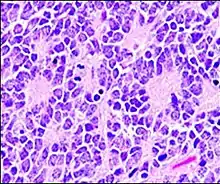

A Flexner–Wintersteiner rosette is a spoke-and-wheel shaped cell formation seen in retinoblastoma and certain other ophthalmic tumors.[3]

Unlike the center of the Homer Wright rosette, the central lumen is devoid of fiber-rich neuropil. The defining feature of this rosette is central extension of cytoplasmic projections of the surrounding cells. Like the Homer Wright rosette, the Flexner–Wintersteiner rosette represents a specific form of tumor differentiation.[5][6][7][8] Electron microscopy reveals that the tumor cells forming the Flexner–Wintersteiner rosette have ultrastructural features of primitive photoreceptor cells.[9] Furthermore, the rosette lumen shows similar staining patterns as in rods and cones,[10] suggesting that Flexner–Wintersteiner rosettes represent a specific form of retinal differentiation. In addition to being a characteristic finding in retinoblastomas, Flexner–Wintersteiner rosettes may also be found in pinealoblastomas and medulloepitheliomas.[5]

Flexner–Wintersteiner rosettes were first described by Simon Flexner (1863–1946), a physician, scientist, administrator, and professor of experimental pathology at the University of Pennsylvania (1899–1903). Flexner noted characteristic clusters of cells in an infantile eye tumor which he called retinoepithelioma.[11][12][13] A few years later, in 1897, Austrian ophthalmologist Hugo Wintersteiner (1865–1946) confirmed Flexner's observations and noted that the cell clusters resembled rods and cones.[14] These characteristic rosette formations were subsequently recognized as important features of retinoblastomas.

Micrograph of perivascular pseudorosettes

Micrograph of perivascular pseudorosettes Structure of a perivascular pseudorosette